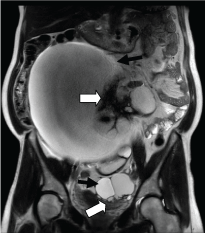

On MRI, the bilateral ovarian cystic masses had thick walls which were hypointense on T2 (Figure 3) and demonstrated minimal enhancement after gadolinium injection, consistent with a fibrous component, being more prominent in the right-sided lesion. The solid peritoneal lesions demonstrated rapid hypervascular enhancement, similar to normal splenic tissue (Figure 4).

Figure 3: T2 coronal MRI image showed predominantly cystic, bilateral ovarian masses (black arrows). There were hypointense solid components (thick white arrows) consistent with papillary projections or fibrous tissue, more prominent in the larger right mass. View Figure 3

Figure 4: a,b,c) Sagittal T1 images of MRI performed before (a) and after gadolinium injection in arterial phase (b) and after several minutes (c) showed that the solid peritoneal lesions were initially slightly hypointense compared to the soft tissue, underwent rapid intense contrast enhancement and retained homogeneous enhancement in the late phase (black arrow in a, b and c). Of note, minimal mural enhancement of right (dashed white arrow in a, b and c) and left (white arrow in a, b and c) ovarian cystic masses. View Figure 4

Based on the MR imaging, the bilateral ovarian lesions were considered to be non-malignant, such as cystadenomas or cystadenofibromas, possibly with some borderline characteristics. Peritoneal splenosis was strongly suggested.